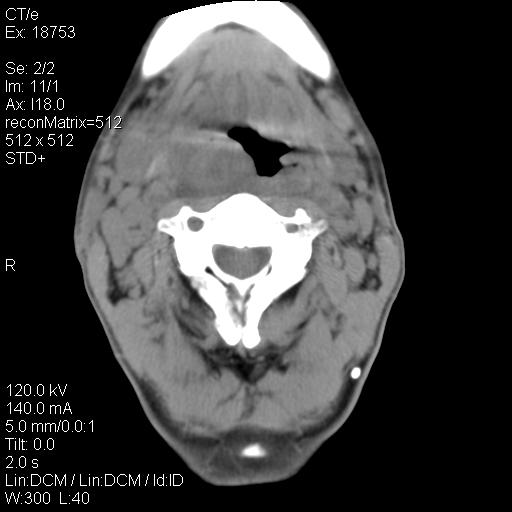

标题: CT21693:男 58岁 右侧咽部疼她2天余 PE:右侧扁桃体肿大 压痛 [打印本页]

标题: CT21693:男 58岁 右侧咽部疼她2天余 PE:右侧扁桃体肿大 压痛

右化脓性扁桃体炎症伴咽后壁脓肿形成.

结合病史,考虑感染性病变;建议抗炎治疗复查排除肿瘤性病变。

弥漫性肿胀,与周围组织分界不清,发病急,有明显症状,考虑:感染性病变! 抗炎后复查。